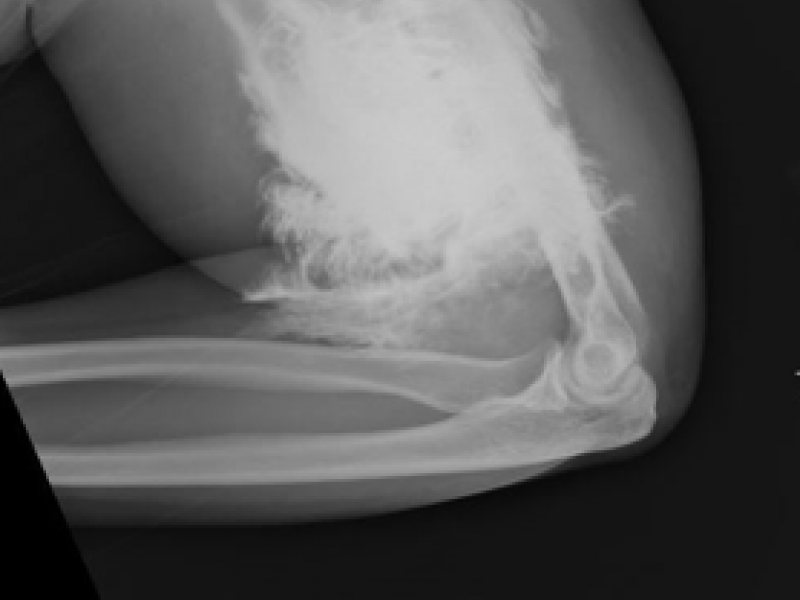

A 30 year old male presents with a displaced right ankle